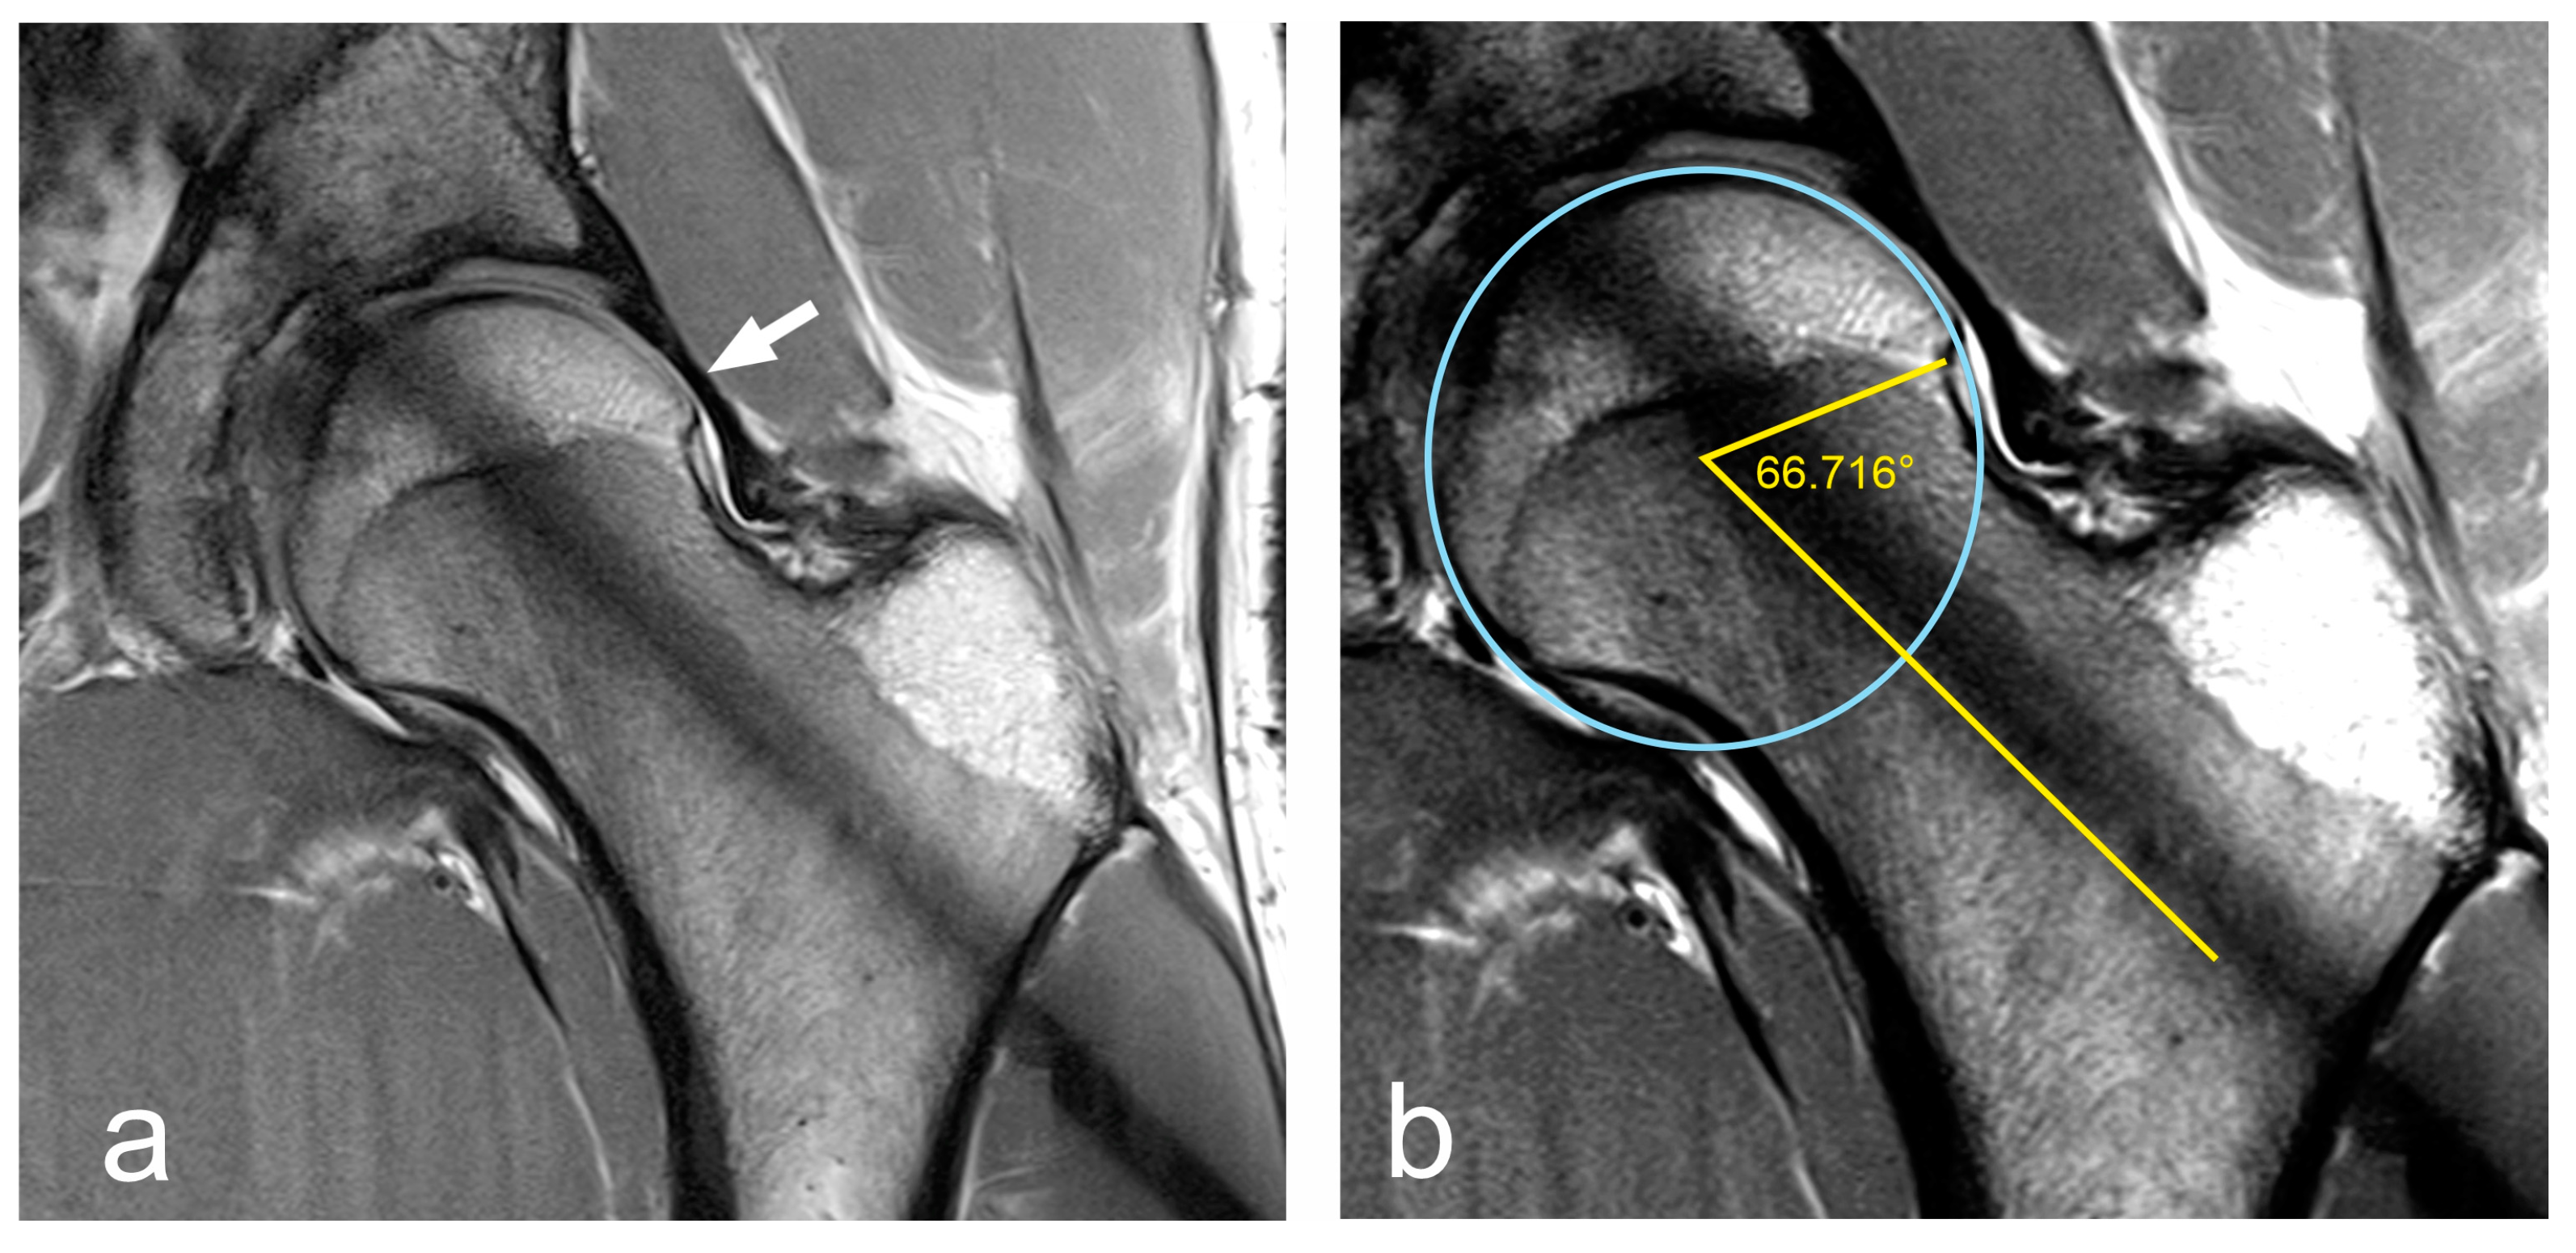

2.2. Imaging Procedures

- Irregularity at the femoral head–neck junction.

- Alpha angle > 60°.

- Nötzli, H.P.; Wyss, T.F.; Stoecklin, C.H.; Schmid, M.R.; Treiber, K.; Hodler, J. The contour of the femoral head-neck junction as a predictor for the risk of anterior impingement. J. Bone Jt. Surg. Br. Vol. 2002, 84, 556–560. [Google Scholar] [CrossRef]

- Agricola, R.; Waarsing, J.H.; Thomas, G.E.; Carr, A.J.; Reijman, M.; Bierma-Zeinstra, S.M.A.; Glyn-Jones, S.; Weinans, H.; Arden, N.K. Cam impingement: Defining the presence of a cam deformity by the alpha angle: Data from the CHECK cohort and Chingford cohort. Osteoarthr. Cartil. 2014, 22, 218–225. [Google Scholar] [CrossRef]

- Barrientos, C.; Barahona, M.; Diaz, J.; Brañes, J.; Chaparro, F.; Hinzpeter, J. Is there a pathological alpha angle for hip impingement? A diagnostic test study. J. Hip Preserv. Surg. 2016, 3, 223–228. [Google Scholar] [CrossRef]